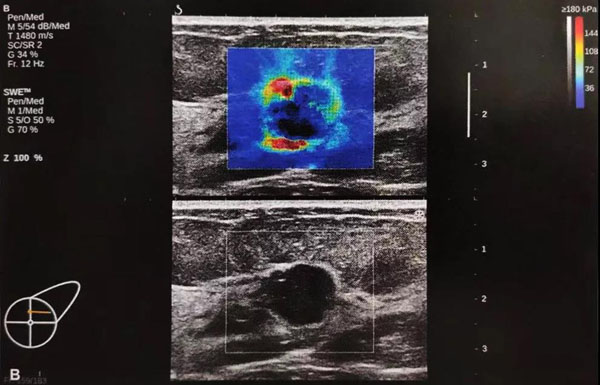

“E超”是一种全新的超声成像模式,具有独有的极速E-成像技术,能够实时、全幅、全定量的进行软组织硬度测量剪切波弹性成像,用超声波触诊内脏器官的硬度,并通过不同的颜色和精确地硬度值来反应所“触诊”部位的硬度,完成传统超声(B超)不能实现的组织定性分析,得到组织的弹性模量绝对值,真正实现无创、超声弹性成像定量分析,为鉴别肿瘤的良恶性提供客观、量化的诊断依据,可减少80%不必要穿刺,是目前世界上先进的新型超声诊断技术。

“E超”在各个学科已有广泛应用,它能够对肝脏、胰腺、脾脏、肾脏、前列腺、子宫、卵巢、甲状腺、乳腺、淋巴结、肌肉、肌腱、血管、神经、淋巴结等组织器官进行弹性定量分析。可以全面应用于乳腺、甲状腺、肝脏、前列腺等人体各组织器官筛查,鉴别良、恶性肿块的性质,与病理学切片相媲美,避免组织穿刺活检细胞学分析的痛苦。